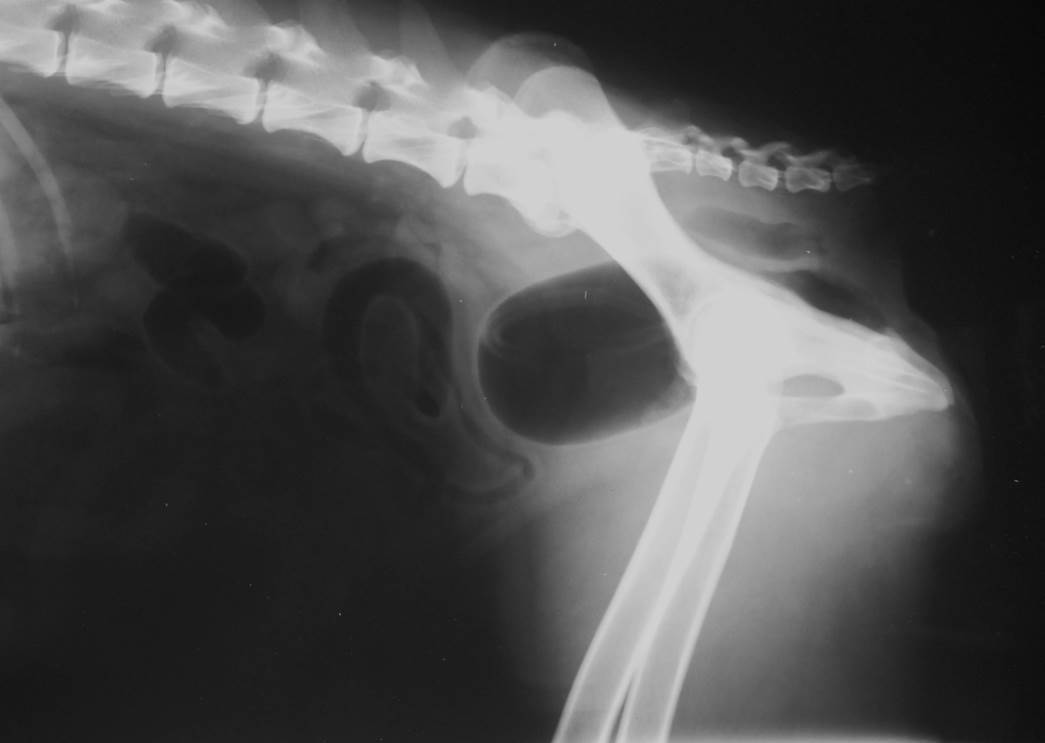

Case Beaver

Discuss this case?

•DCC and retrograde urethrogram

–poor quality urethrogram, poor filling of urethra, air bubbles ++. This study is important to rule out strictures, urethral plug, calculi.

•Bladder has identical appearance on both films

–small (likely not possible to distend further or at least not safely)

–thickened wall

–repeat retrograde to rule out stricture/urolith but doesn’t seem obstructed

–urinalysis especially for urine culture in case UTI following recent catheterisation during last episode of clinical signs

•Diagnosis: likely to be FLUTD, idiopathic cystitis